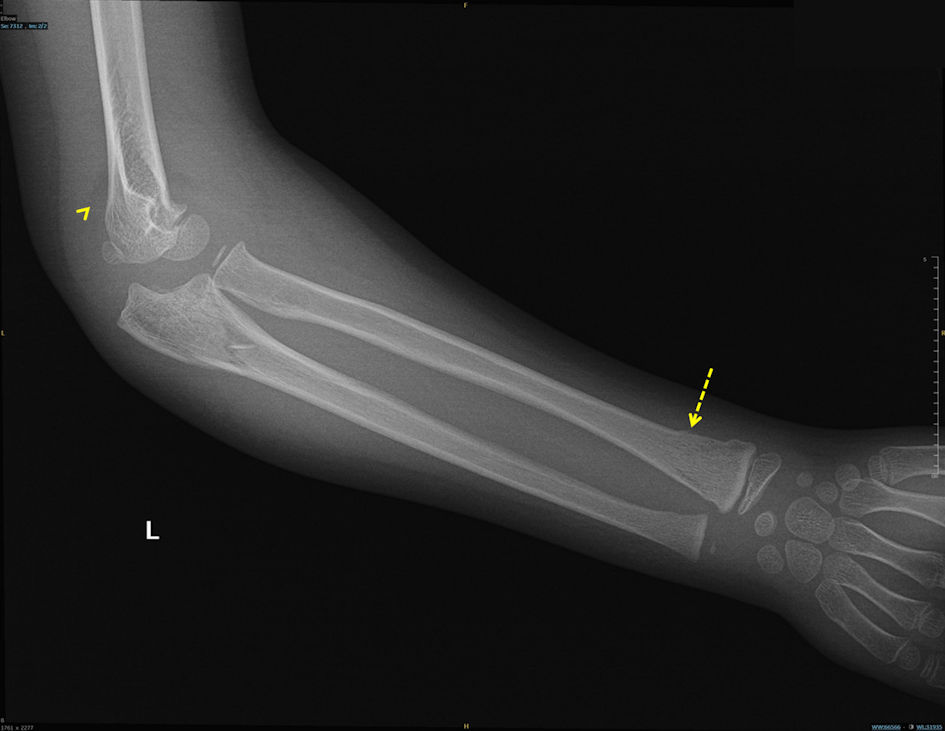

Capillary refill was delayed (3 - 4 s), and the radial pulse was absent on palpation and undetectable by Doppler. However, pulse oximetry readings were obtainable from the left thumb, middle, and ring fingers. She was afebrile and hemodynamically stable except for tachycardia (heart rate 120 beats per minute (bpm)). Urgent radiographs demonstrated non-displaced proximal ulnar and distal radial fractures of the left forearm (Figs. 1, 2).

Click for large image

Figure 1. Lateral elbow radiograph demonstrating the posterior fat pad sign (arrowhead) and distal radial fracture (dashed arrow).